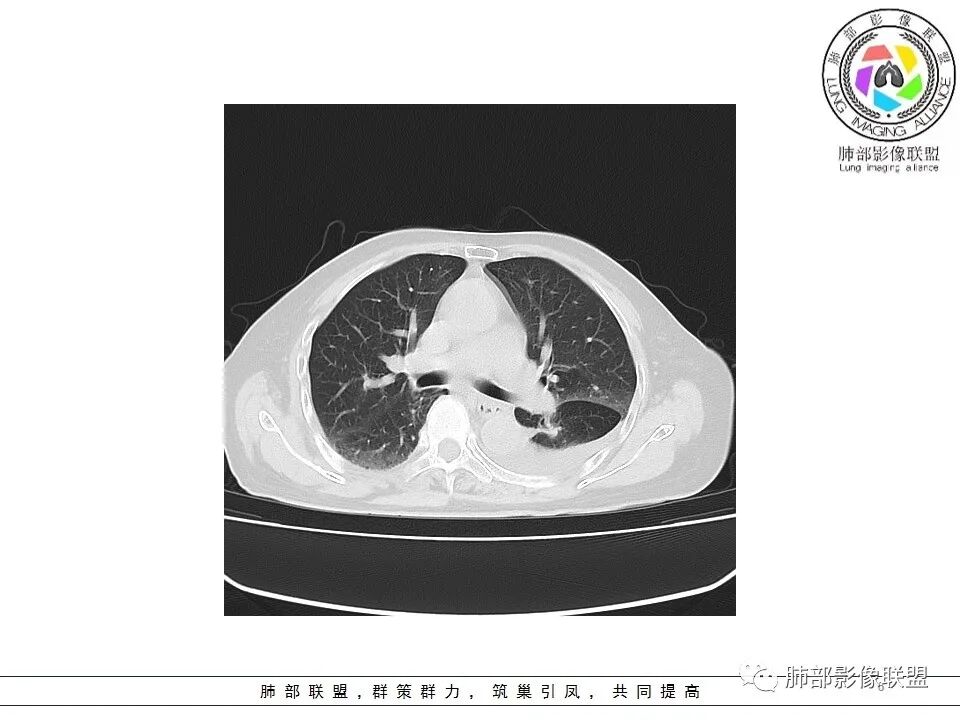

一切∮随缘: 左肺下叶脊柱旁可见大片状实变,跨多个叶段,宽基底与胸膜相贴,胸膜下可见积液,周围伴有空洞,平扫密实欠均匀,增强扫描可见低密度坏死,及血管束穿行,临床:女性,反复咳嗽咳痰7天,余未提示异常,无实验室指标,考虑:慢性脓肿(OP),放线菌?奴卡?腺癌?完善支气管镜,穿刺送培养,病理学检查。

?? 玫: 女,78岁,反复咳嗽,咳痰一周,左侧胸腔积液,贫血,左肺下叶片状实变影,边界清晰,病灶呈宽基底与胸膜相连,病灶内密度不均,增强扫描呈不均匀性强化,病灶内坏死,考虑肺脓肿可能,鉴别鳞癌,腺癌。

宇宙: 左肺下叶后基底段肿块,边缘毛糙,后基底段支气管阻塞,明显不均匀渐进强化,其内血管清晰自然,可见坏死灶,部分边界清,左侧胸水,考虑炎性病变,鉴别腺癌

飞鹰行动: 女,78岁,反复咳嗽,咳痰七天,左肺下叶纵膈旁团片状实变影,边界清晰,局部膨胀性生长,病灶内密度不均,增强扫描病灶内呈不均匀性强化,部分坏死区边界不清晰,内可见血管造影征,部分坏死区边界清晰,可见环形强化,感染性病变是有的,需要警惕合并占位,腺癌伴感染?

小兜: 女,78岁 反复咳嗽咳痰7天,左肺下叶脊柱旁实变影,平扫密度不均,内部可见低密度灶,增强扫描明显不均匀强化,内部血管走行自然,可见多发低密度坏死区,坏死区边界清晰,少量胸水,考虑脓肿

老年女性,急性发病,短病程病史。左肺下叶实变影,肺叶体积缩小,周围有带状不一致密度影。单独发生于左侧的胸腔积液渗出液多见。   影像上病灶重建后长轴呈楔形,而非类圆形,边缘平直,符合肺叶形态(与横断位膨隆并不一致),从整体形态上支持炎性病变;   病灶内血管走形自然,无受侵犯、受推移迹象,不大符合鳞癌等破坏性较强的肿瘤性病变。女性患者鳞癌也少见。   病灶内坏死腔内壁清楚光滑,薄环状强化带,支持炎性、尤其是化脓性病变。肺腺癌这样的坏死少见。   病灶近端支气管虽然堵塞,但是支气管走形自然,壁无明显破坏,腔内粘液栓堵塞为主,病灶外周大,内带小,局部无膨隆迹象,不符合近端支气管肺癌堵塞所致表现;也不符合外周肿块朝内带推进表现。   综合分析:符合炎性病变,不支持恶性肿瘤性改变